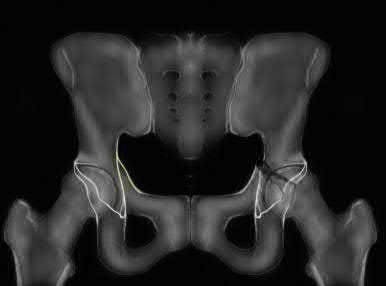

Question 11

A poly-trauma patient presents hemodynamically unstable with an anteroposterior compression (APC-III) pelvic ring injury. A circumferential pelvic binder is requested to reduce pelvic volume and control hemorrhage. To be anatomically effective, the binder must be centered precisely over which of the following landmarks?

Explanation

For optimal mechanical advantage and effective reduction of an 'open book' pelvic fracture (APC type), a pelvic binder must be applied directly over the greater trochanters of the femurs. Applying it higher, such as over the iliac crests, is a common error that fails to adequately close the pelvic ring and can paradoxically open the true pelvis.